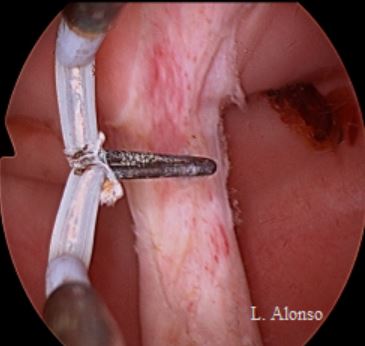

La técnica quirúrgica con preservación del septo cervical fue descrita por Rock [Rock, J. A., et al. (1999). «Hysteroscopic metroplasty of the Class Va uterus with preservation of the cervical septum.» Fertil Steril 72(5): 942-945.] en una serie de 21 pacientes. La descripción de la técnica es la siguiente: tras la dilatación cervical se introduce una sonda de Foley o un dilatador en una de las cavidades que sirven como guía para la sección de la parte corporal del septo. Posteriormente introducían el resectoscopio con una asa de Collins en la otra cavidad, y se incidía el septo intrauterino a nivel supracervical. El catéter de Foley servía como guía, y una vez iniciada la unificación de las cavidades se procedía como en cualquier otra metroplastia.

Probablemente la primera referencia que podemos encontrar respecto a la sección del septo cervical es la de Vercellini [Vercellini, P., et al. (1994). «A modified technique for correction of the complete septate uterus.» Acta Obstet Gynecol Scand 73(5): 425-428.] que realizó la sección del septo cervical con tijeras de Metzenbaun en 7 pacientes en la que tuvieron grandes dificultades para crear la comunicación inicial entre las dos cavidades endometriales. Posteriormente compararon los resultados de estas pacientes con otro grupo de 9 pacientes en las que se respeto este septo intracervical. No tuvieron complicaciones ni intraopertorias ni obstétricas en relación con la sección del septo cervical. No se realizó cerclaje a ninguna de las pacientes.